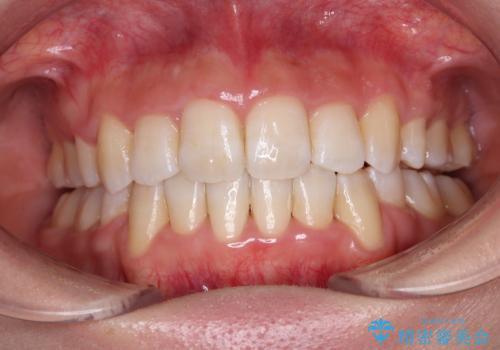

- 上下前歯のデコボコと、それによる磨きづらさを気にして来院された患者様です。

叢生解消のため、上下左右第一小臼歯4本を抜歯し、ワイヤー装置にて矯正治療を行うこととしました。

半年ほどで前歯のデコボコは改善され、汚れの溜まりやすさは解消されました。

抜歯スペースを閉じるために期間がかかりましたが、当初予定通り2年強で終えることができました。